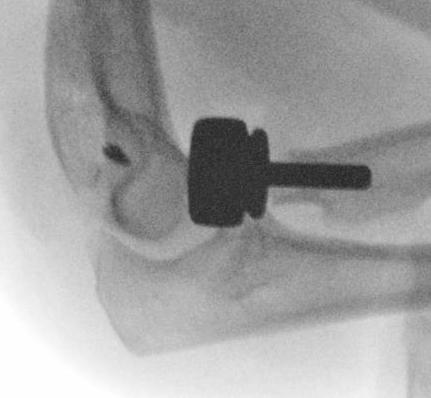

Radial Head Arthroplasty (RHA)

Design

Cobalt chrome / pyrocarbon / titanium

Modular - various head diameter / thickness + various stem sizes + collars to build up radial neck if required

Fixation - press fit v loose fit

Technique Modular Titanium Radial Head Arthroplasty

Lateral approach to elbow / Kaplans or Kocher

- open capsule

- divide annular ligaments

- excise radial head fragments

- use fragments to estimate diameter and thickness of radial head

- if in doubt, downsize

- deliver radial neck

- do not place Hohman retractor anteriorly to protect PIN

- ensure neck cut flat to avoid maltracking

- want 60% contact of radial neck with prosthesis

- insert trial broaches into neck

- insert trial head diameter and neck length

- check no overstuffing on xray

- insert prosthesis

- repair annular ligament

- inspect +/- repair LCL

Overstuffing

| Lesser sigmoid notch | Symmetry of ulnohumeral joint |

|---|---|

|

Radial head shoulder articulate with lesser notch

Ensure no gapping of lateral ulnohumeral joint |